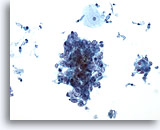

Lavage bronchique

Faible grossissement d’un carcinome indifférencié à grandes cellules.

20x